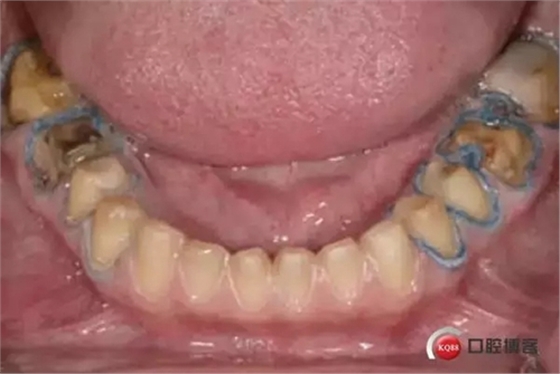

前期準(zhǔn)備:牙體預(yù)備時(shí),沿著牙齦輪廓制備牙齦緣,制備齦上肩臺(tái),盡量減少對(duì)牙齦組織的損傷。

2. 輕輕地將第一根排齦線放置在齦溝內(nèi):可以放置各種類(lèi)型的排齦線(編織線或者針織線)在結(jié)合上皮附著處。排齦線型號(hào)以可以填滿(mǎn)1/2牙齦溝為準(zhǔn)。非浸潤(rùn)止血材料的排齦線(首選)或浸漬止血材料排齦線都可。

3. 確定基牙是否需要填充或者塑形:去除舊的修復(fù)體,評(píng)估基牙是否需要填充或者塑形。在去掉舊的修復(fù)體或者齲壞組織之前,提前進(jìn)行牙體預(yù)備。這是與院校里面的要求相反的,院校里往往要求先進(jìn)行牙體塑形或者先去除舊的修復(fù)體,然后再進(jìn)行牙體預(yù)備。

4. 完成邊緣線的制備: 第一根排齦線可以幫助保護(hù)牙齦組織不被損傷,也可幫助識(shí)別結(jié)合上皮附著處。如果制備齦下肩臺(tái),制備肩臺(tái)至第一根排齦線的冠狀面,距離上皮附著一半的距離。不要損傷牙齦。有各種各樣的器械(Zekrya 牙齦保護(hù)器 by DMG America)可用來(lái)在牙體預(yù)備的時(shí)候退縮牙齦并保護(hù)排齦線。

5. 放置第二根排齦線:選擇一根可以填滿(mǎn)牙齦溝的排齦線。可以觀察到排齦線完全包繞牙體。第二根排齦線往往需要浸漬止血材料: 如果是通透性好的牙冠(二硅酸鋰)選擇氯化鋁止血材料;如果是不透明的冠(金屬冠/烤瓷冠)則選擇和硫酸鐵。注意: 盡管硫酸鐵有效,但是硫酸鐵可以使基牙染色,并可以使通透性好的牙冠透色。